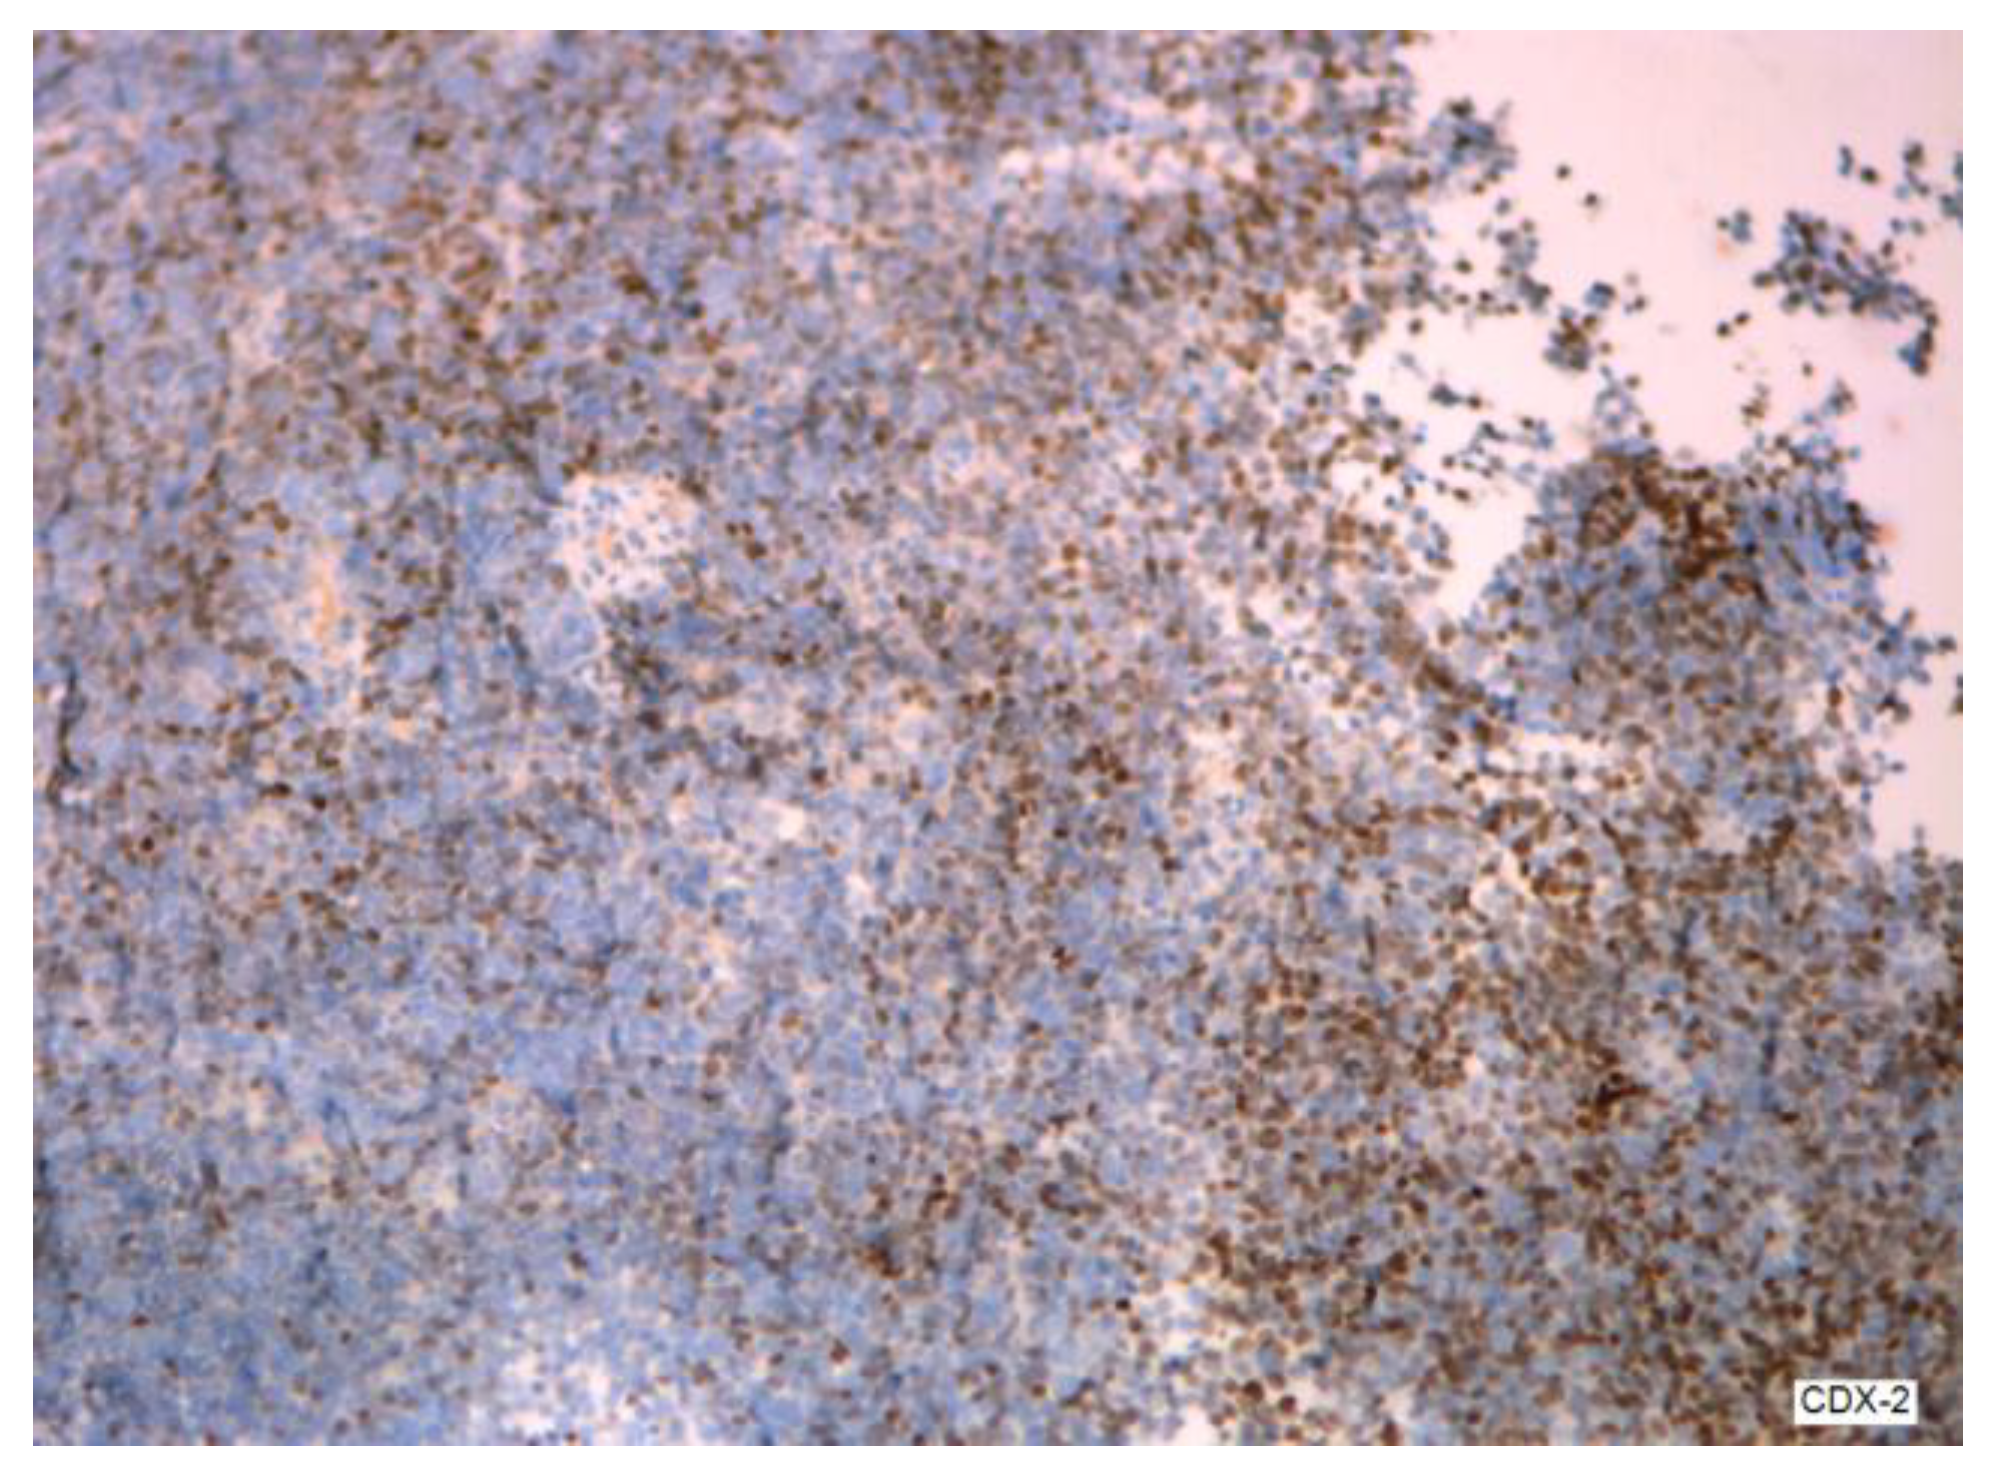

3.2.2. Clinical and Pathology Findings

- Dundr, P.; Singh, N.; Nožičková, B.; Němejcová, K.; Bártů, M.; Stružinská, I. Primary mucinous ovarian tumors vs. ovarian metastases from gastrointestinal tract, pancreas and biliary tree: A review of current problematics. Diagn. Pathol. 2021, 16, 20. [Google Scholar] [CrossRef] [PubMed]

- Wang, B.; Yao, J.; Ma, R.; Liu, D.; Lu, Y.; Shi, G.; An, L.; Xia, A.; Chen, F.; Pang, S.; et al. The mutational landscape and prognostic indicators of pseudomyxoma peritonei originating from the ovary. Int. J. Cancer 2021, 148, 2036–2047. [Google Scholar] [CrossRef]